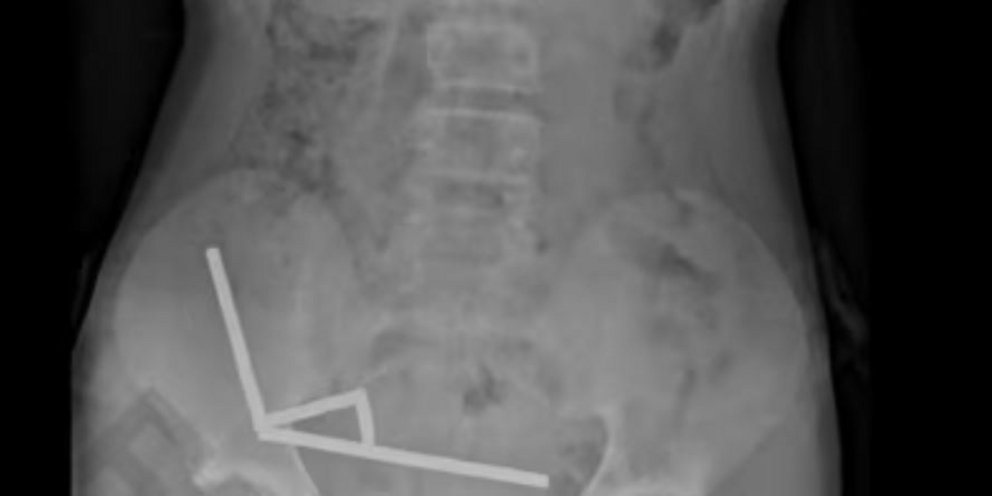

Ο έφηβος υποβλήθηκε σε επέμβαση και χρειάστηκε να του αφαιρεθούν τμήματα του εντέρου του που είχαν υποστεί νέκρωση, αφού κατάπιε περίπου 100 ισχυρούς μαγνήτες νεοδυμίου, μεγέθους περίπου 5χ2 χιλιοστών, μία εβδομάδα νωρίτερα, ανέφερε η ιατρική επιθεώρηση. Έκτοτε, πήρε εξιτήριο και επέστρεψε σπίτι του.